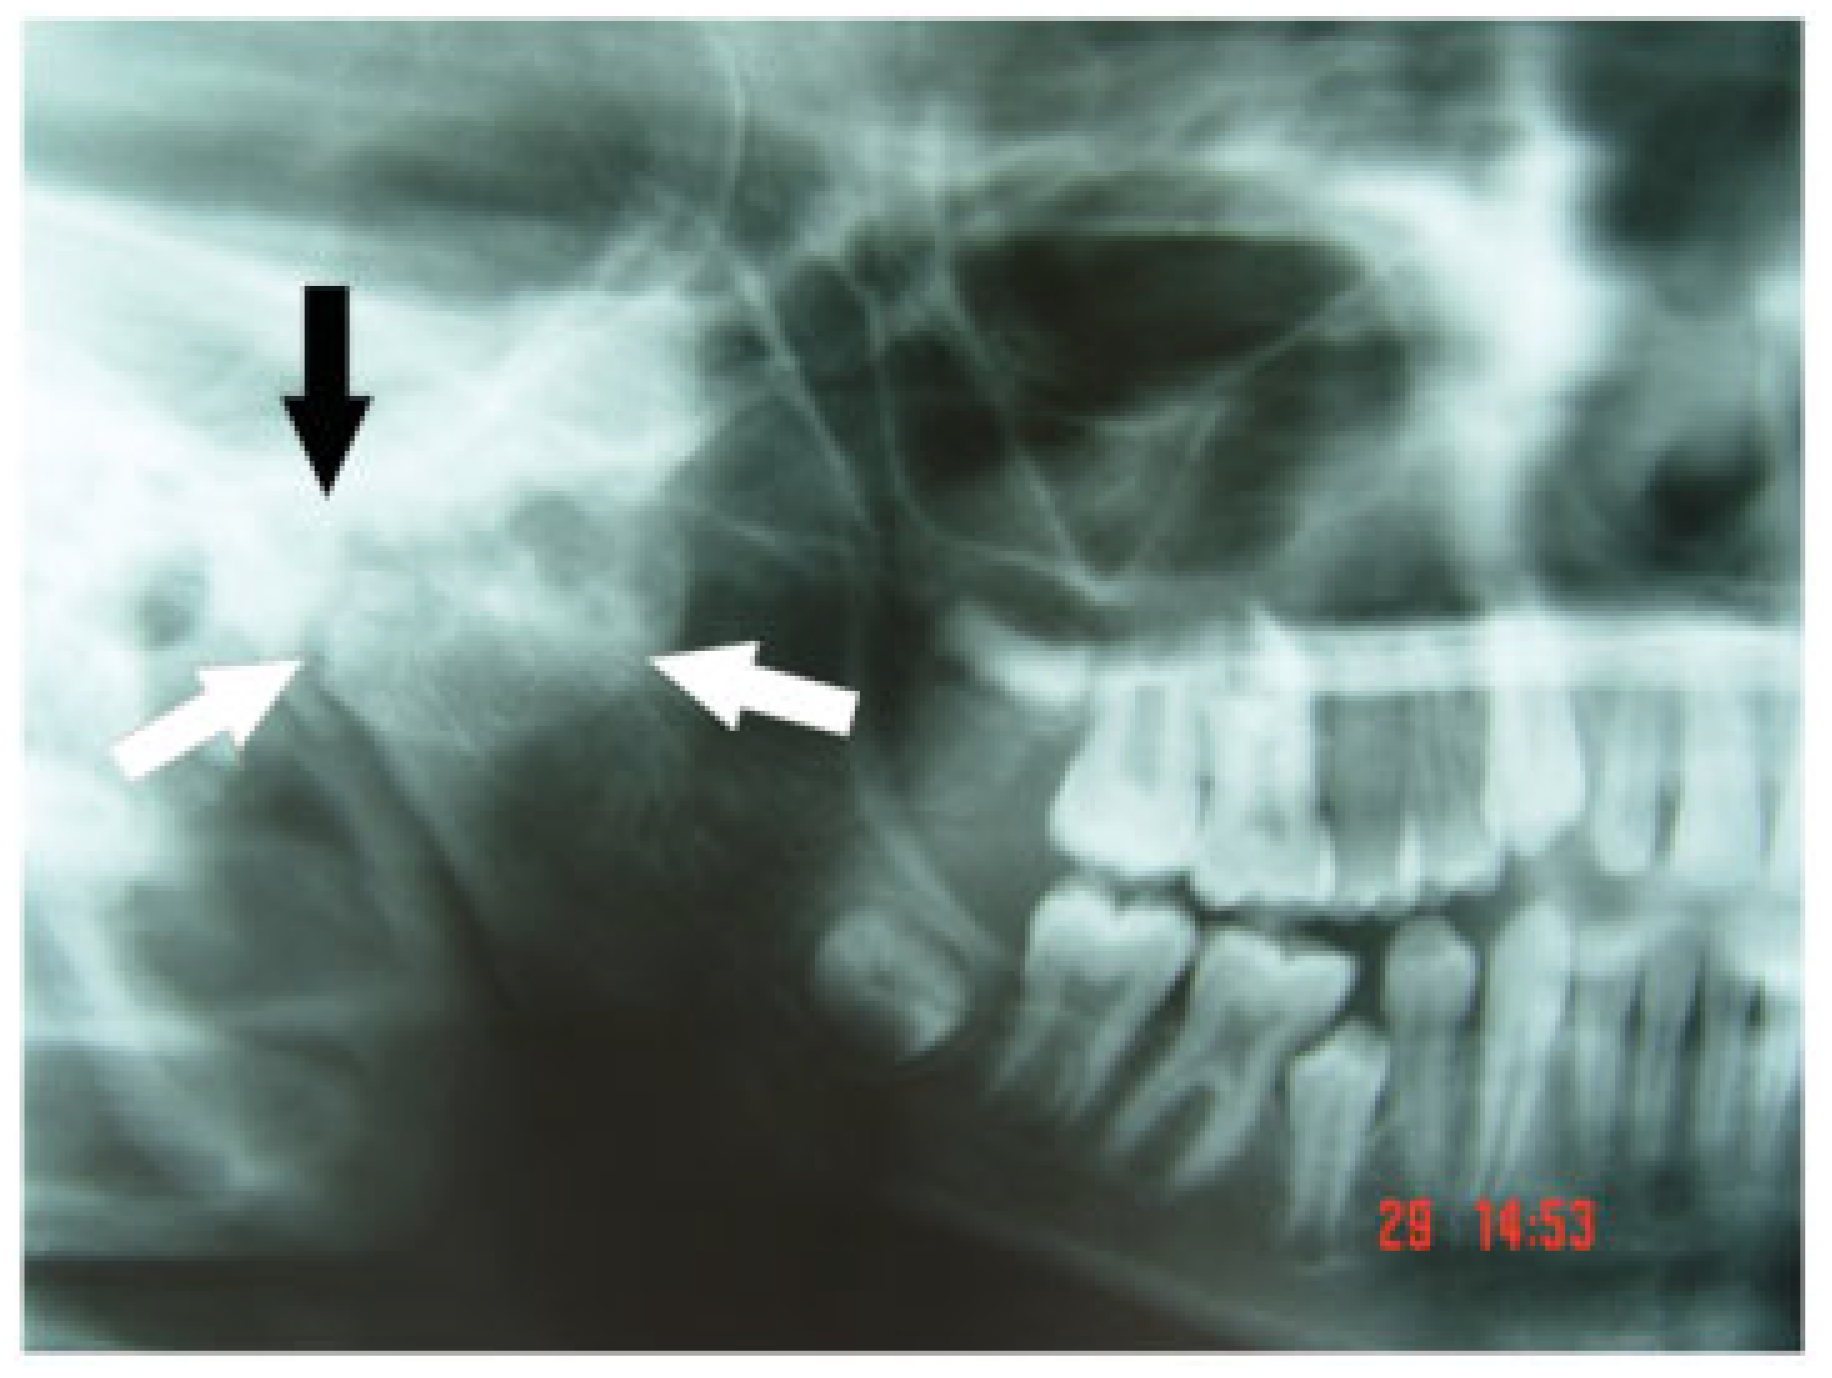

A young boy presented to the Maxillofacial Surgery Service with a severe limitation in mouth opening (Figure 1). He had problems with eating and difficulty in maintaining oral hygiene. He displayed facial asymmetry with a shift of both his facial and dental midlines to the right. There was also an alteration of the occlusal cant of the maxilla with the left side being lower than the right. He had fallen as a child some years previously and fractured the right mandibular condyle. An orthopantomogram radiograph (OPG; Figure 2) showed marked changes in TMJ anatomy and architecture on the affected right side and a hypertrophied right coronoid process.

Figure 2. Right side of an orthopantomogram showing the periphery of the mass of bone (white arrows) in the region of the right temporomandibular joint (black arrow).